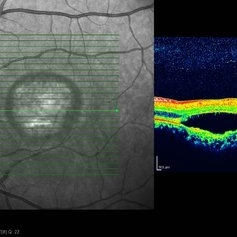

Best Disease Best DiseaseMar 9 2013 by Hamid Ahmadieh, MD OCT of the right eye of a 49-year-old man with decreased VA due to advanced Best disease. Photographer: Soodabeh Fooladin, Negah Eye Center, Tehran Imaging device: Heidelberg Spectralis Condition/keywords: Best disease, optical coherence tomography (OCT)

Best Disease Best DiseaseMar 9 2013 by Hamid Ahmadieh, MD OCT of the left eye of a 49-year-old man with decreased VA due to advanced Best disease. Photographer: Soodabeh Fooladin, Negah Eye Center, Tehran Imaging device: Heidelberg Spectralis Condition/keywords: Best disease, optical coherence tomography (OCT)